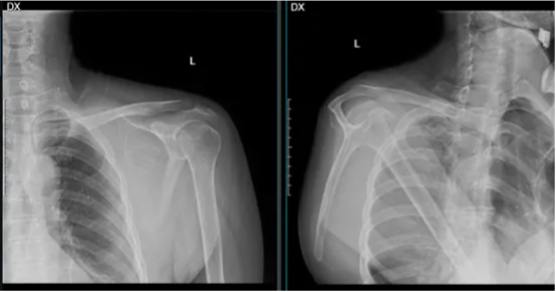

图示:术前X线检查,左侧肩胛骨周围软组织增厚,似肿瘤影